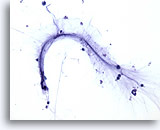

Lavado bronquial

Se muestra la naturaleza en forma de cintas de estas grandes hifas.

40x